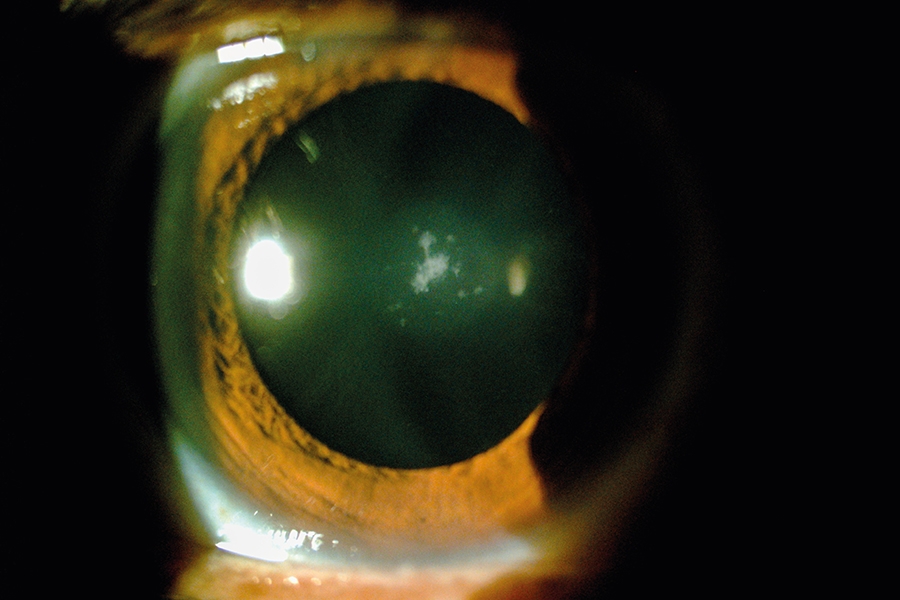

5.3. Catarata Subcapsular Posterior

Es cuando la opacidad se produce en la cápsula del cristalino, este tipo de cataratas suelen progresar con bastante rapidez y presentan pocos síntomas hasta que están desarrolladas.

Son más frecuentes en personas jóvenes.